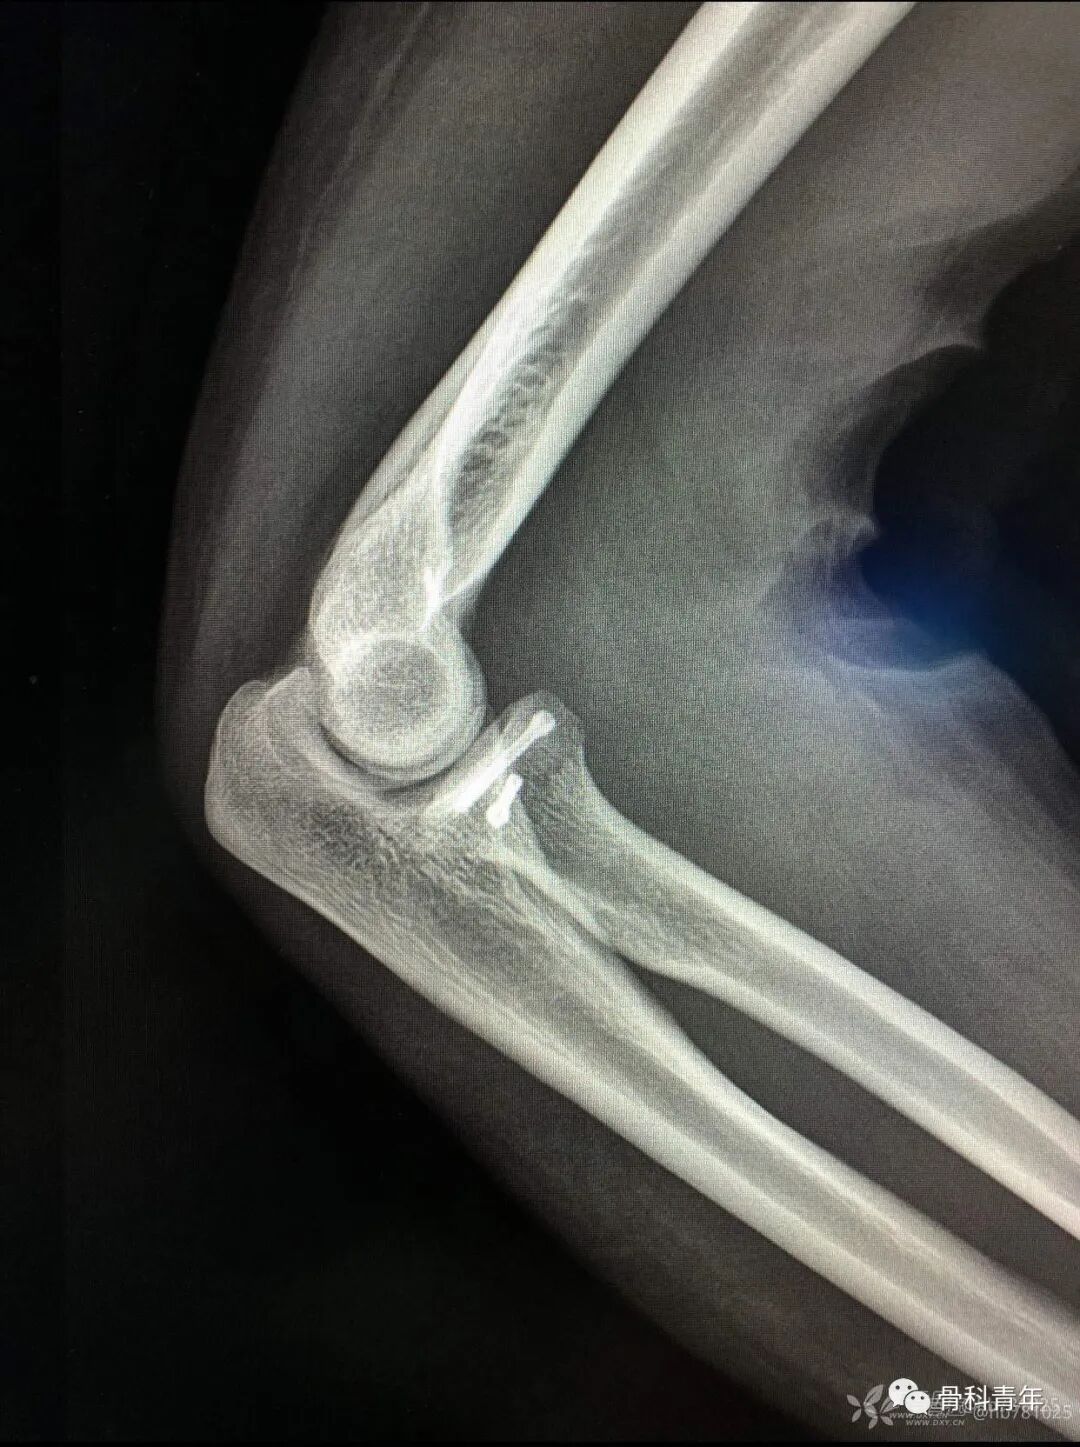

23.尺骨鹰嘴骨折